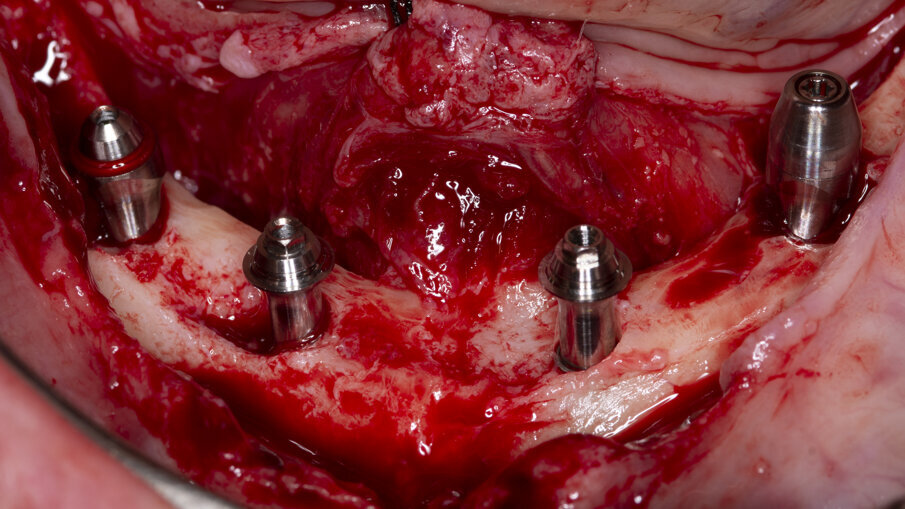

Nel mascellare inferiore si inseriscono 4 impianti Advan GTB (Figg. 6, 7): in posizione 3.5, un impianto inclinato di 3.6x10.5 mm con un multiunit abutment di 4.5 mm inclinato di 30°; in posizione 3.2 un impianto di 3.6x7.5 mm con un multi-unit abutment dritto di 5.5 mm; in posizione 4.2 un impianto di 3.6x7.5 mm con un multi-unit abutment dritto di 6.5 mm; e in posizione 4.5, un impianto inclinato di 3.6x9 mm con un multi-unit abutment di 4.5 mm inclinato di 30°. La profondità sottocrestale degli impianti varia dai 2 ai 3 mm. Lo stesso giorno, si realizza un carico immediato con due protesi avvitate provvisorie in resina. Si controlla il paziente dopo una settimana per la rimozione dei punti di sutura, dopo un mese e dopo 3 mesi e mezzo dall’intervento, momento in cui si realizza una ortopantomografia, si verifica l’osteointegrazione di tutti gli impianti e si prendono le impronte per la fabbricazione delle protesi definitive, consistendo queste ultime in strutture ibride avvitate con un nucleo metallico anatomico e monconizzato, corone singole di disilicato di litio cementate e gengiva artificiale in composito rosa (Fig. 8).

Fig. 6 - Fotografia intraoperatoria che evidenzia il posizionamento sotto-crestale degli impianti GTB inseriti nel mascellare inferiore. 6a: impianto in posizione 4.5. 6b: impianto in posizione 3.5. 6c: impianto in posizione 4.2. 6d: impianto in posizione 3.2.